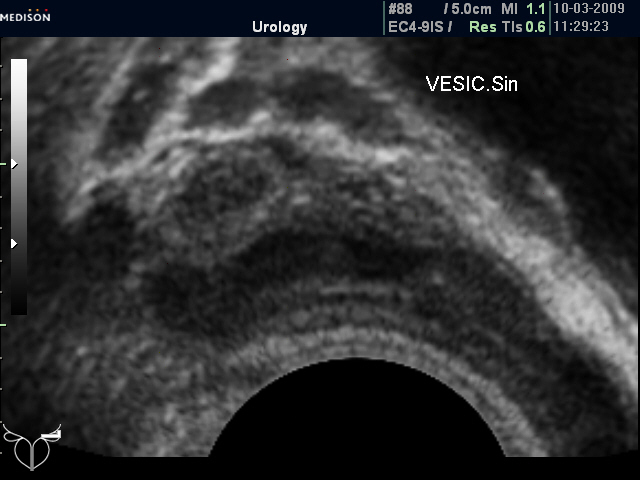

Но не всегда норма СП при ТА УЗИ подтверждается при ТРУЗИ (фото 3-6)

"Нормальные" СП (ТА УЗИ)

"Нормальные" СП (ТР УЗИ)